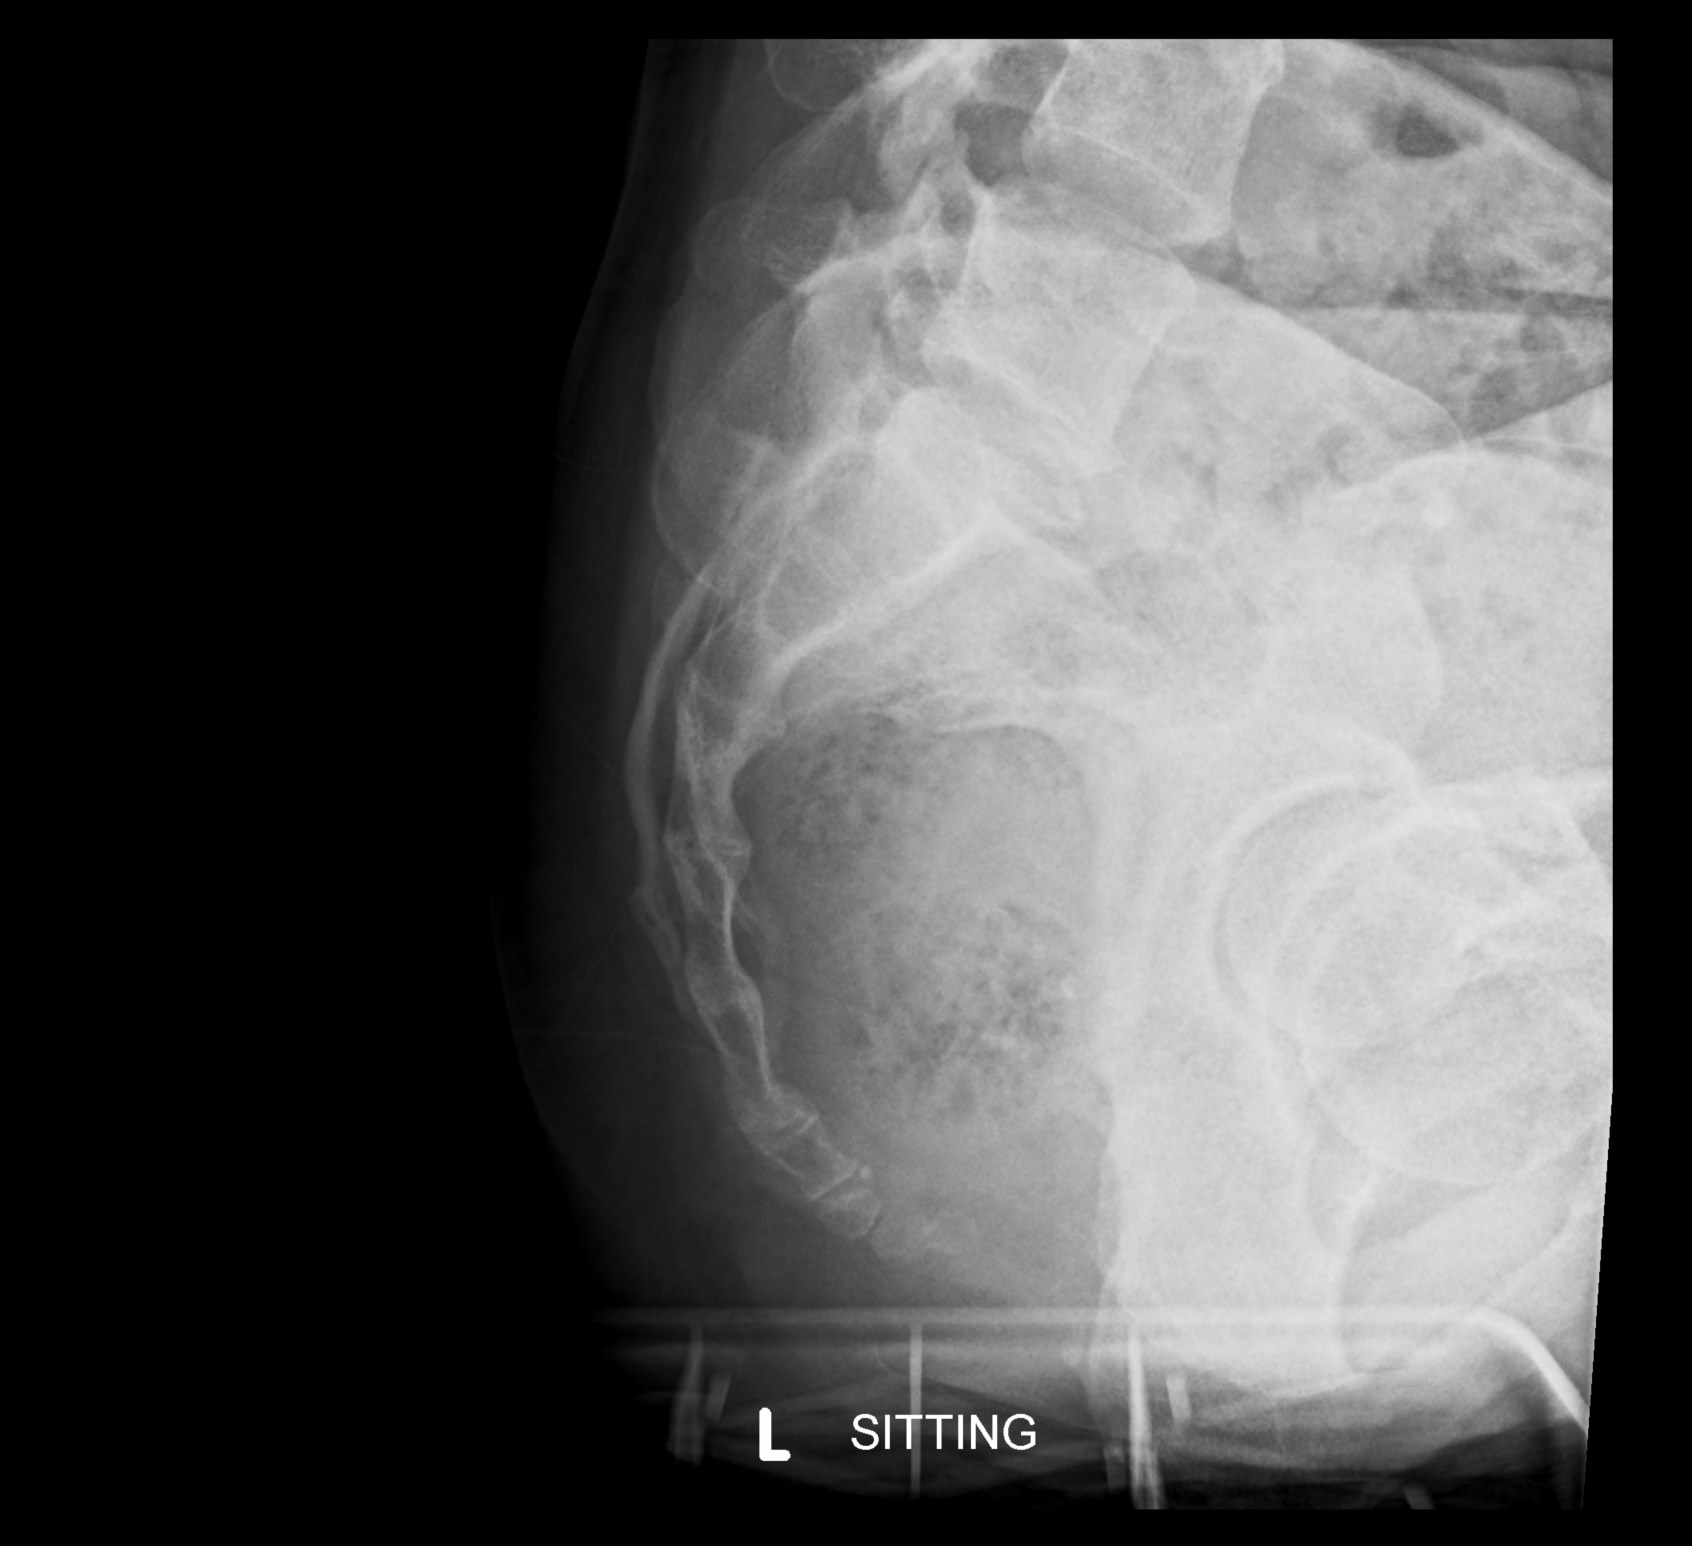

Sitting X-rays (see Figures 1 & 2) can be helpful.

Fig 2. Patient positioning and setup for seated lateral radiography of the coccyx [3]. Illustration shows the patient in a seated position on a hard-surface stool with their thighs horizontal, which may require placing their feet on a footrest, depending on the height of the stool. They are then instructed to lean back to the point of maximum tenderness and hold in this position for image acquisition.

Fig 3. Seated lateral coccyx radiograph.